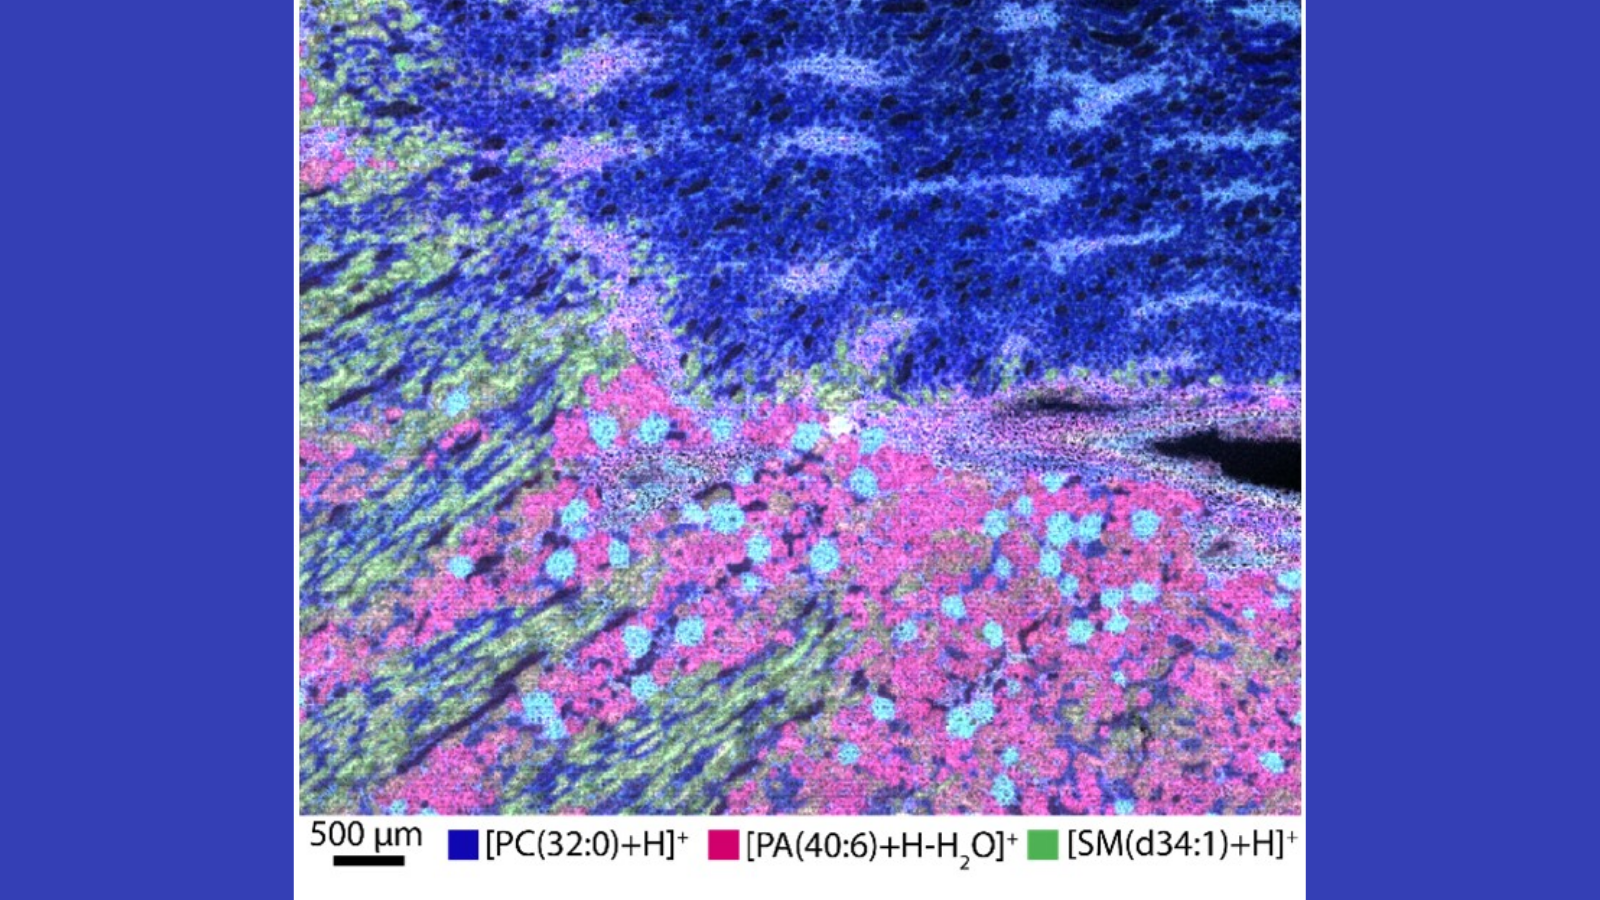

Maps of imaging mass spectrometry data from rat brain, courtesy of Hang Hu at PNNL

MALDI mass spectrometry image that shows where three kinds of lipids are in different parts of a human male kidney, courtesy of Dr. Elizabeth Neuman of Vanderbilt